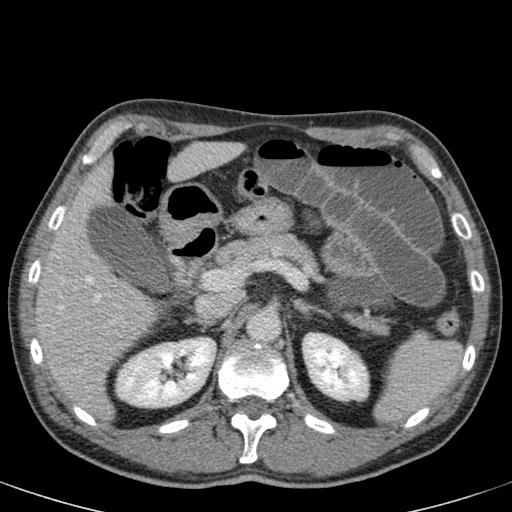

Bên trái là các hình ảnh CT bổ sung của cùng bệnh nhân nêu trên.

Hãy quan sát các hình ảnh này, tìm kiếm các dấu hiệu chính rồi tiếp tục.

Đầu tiên, chúng ta thấy đại tràng xuống xẹp và đại tràng lên không giãn, do đó đây không thể là xoắn đại tràng sigma.

Thứ hai, chúng ta thấy một cấu trúc hình mỏ chim ở góc phần tư dưới bên phải, đây là vị trí xoắn của ruột.

Ở góc phần tư dưới bên trái, chúng ta thấy manh tràng giãn.

Tái tạo ảnh mặt phẳng coronal có thể rất hữu ích trong việc thể hiện toàn cảnh tổn thương.

Bên trái, chúng ta thấy đại tràng lên và đại tràng xuống không giãn (mũi tên thẳng) và điểm chuyển tiếp của xoắn (mũi tên cong).

Xoắn manh tràng xảy ra do manh tràng xoắn quanh đại tràng lên, dẫn đến tắc ruột non.

Mạc treo ruột có nền hẹp và dài là yếu tố thuận lợi gây xoắn.

Xoay ruột giữa không hoàn toàn là một yếu tố nguy cơ.

Nhồi máu thường là hậu quả của ứ trệ tĩnh mạch, trong khi nguồn cung cấp động mạch hiếm khi bị ảnh hưởng.

Xoắn manh tràng chiếm khoảng 25% các trường hợp xoắn đại tràng.